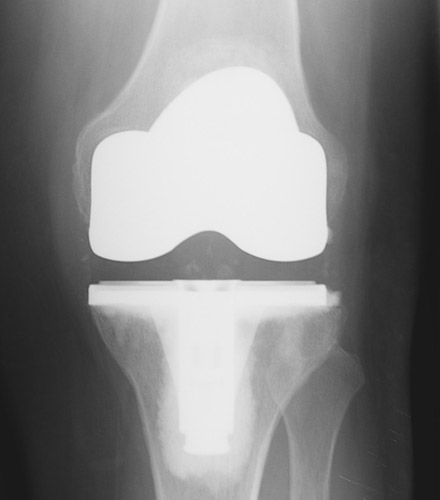

- Same reliable surgical implants as Traditional Knee Replacement. Much has been learned about implant design in the nearly 40-year history of contemporary knee replacement. Minimally-invasive quadriceps-sparing total knee replacement is an evolution of surgical technique which permits the use of time-tested implant designs (see figures 3 and 4). This gives some reassurance that while the surgical approach is new the implants themselves have a good proven track record.

- Same reliable surgical implants as Traditional Knee Replacement. Much has been learned about implant design in the nearly 40-year history of contemporary knee replacement. Minimally-invasive quadriceps-sparing total knee replacement is an evolution of surgical technique which permits the use of time-tested implant designs. This gives some reassurance that while the surgical approach is new the implants themselves have a good proven track record.

Long considered the “gold standard” operation for knee arthritis total knee replacement is still by far the most commonly-performed joint replacement procedure (see figure 13). It is most suitable for middle-aged and older people who have arthritis in more than one compartment of the knee (see figures 14 and 15) and who do not intend to return to high-impact athletics or heavy labor. Results of this procedure generally are excellent with 90-95% of total knee replacements continuing to function well more than 10 years after surgery.